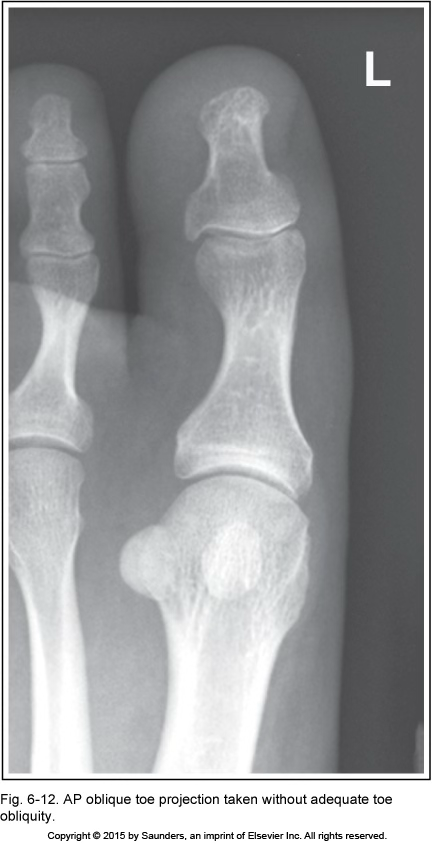

AP oblique toe

accurate positioning

inadequate toe obliquity